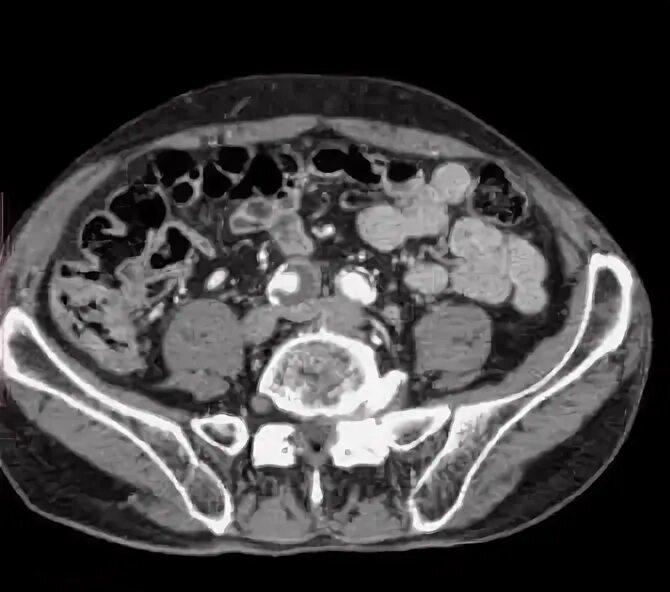

Кт обп омт с контрастированием